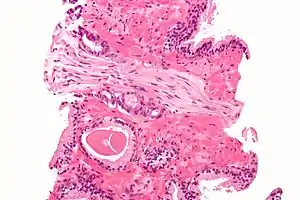

Within a nerve, each axon is surrounded by a layer of connective tissue called the endoneurium. The axons are bundled together into groups called fascicles, and each fascicle is wrapped in a layer of connective tissue called the perineurium. Finally, the entire nerve is wrapped in a layer of connective tissue called the epineurium. Nerve cells (often called neurons) are further classified as sensory, motor, or mixed nerves.

Each nerve is covered on the outside by a dense sheath of connective tissue, the epineurium. Beneath this is a layer of fat cells, the perineurium, which forms a complete sleeve around a bundle of axons. Perineurial septae extend into the nerve and subdivide it into several bundles of fibres. Surrounding each such fibre is the endoneurium. This forms an unbroken tube from the surface of the spinal cord to the level where the axon synapses with its muscle fibres, or ends in sensory receptors. The endoneurium consists of an inner sleeve of material called the glycocalyx and an outer, delicate, meshwork of collagen fibres.[2] Nerves are bundled and often travel along with blood vessels, since the neurons of a nerve have fairly high energy requirements.